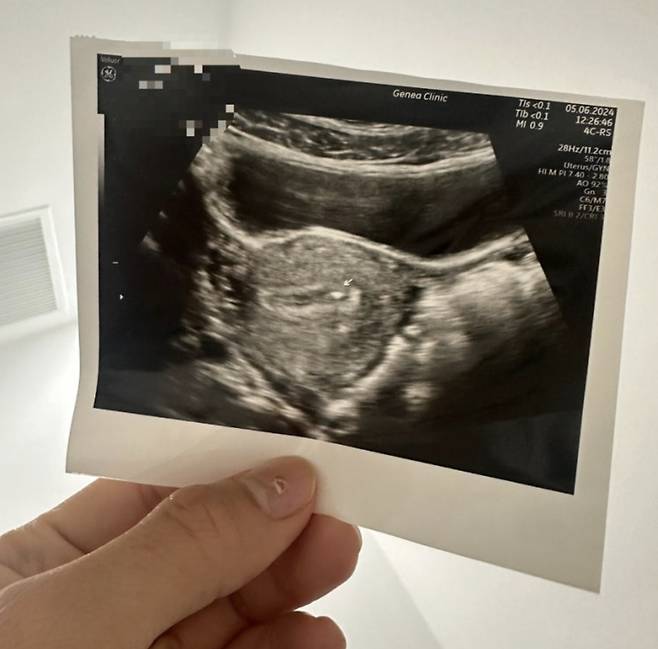

![An ultrasound scan after Sohan received a male embryo at a Thai clinic [SOHAN]](https://img2.daumcdn.net/thumb/R658x0.q70/?fname=https://t1.daumcdn.net/news/202509/10/koreajoongangdaily/20250910070258612xixn.jpg)

She returned to Korea after an injection of the male embryo as a mother expecting a son.